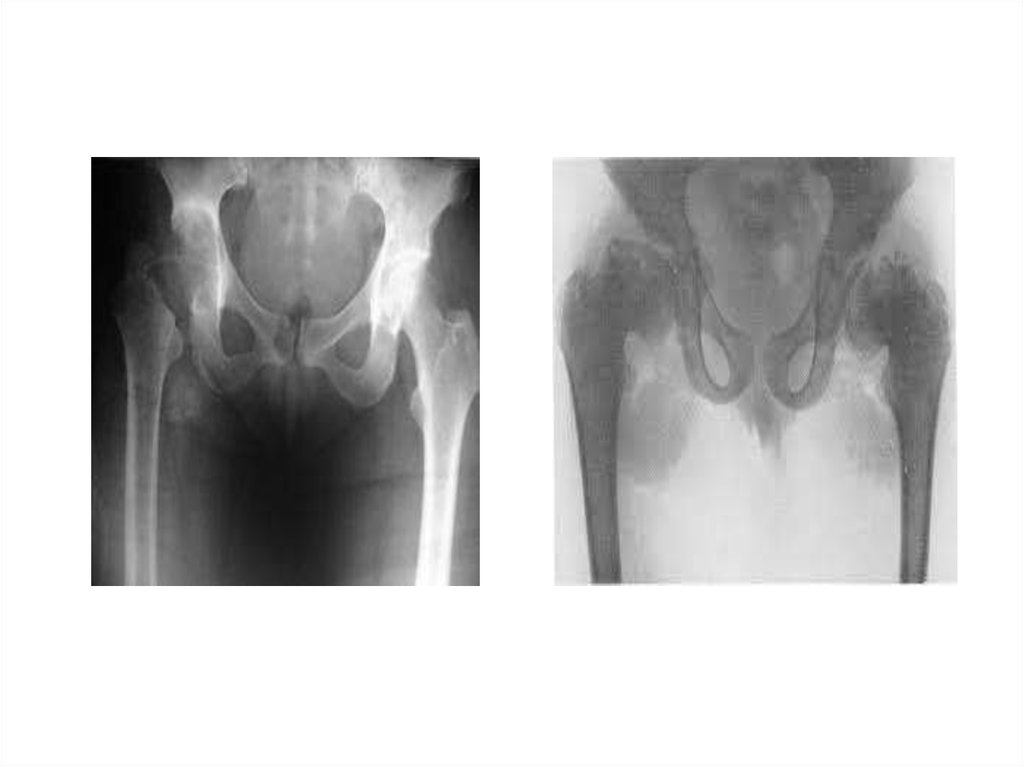

Медицинские аспекты заболеваний: рентгенологическая картина туберкулеза костей

Раздел: Снимки-откровения